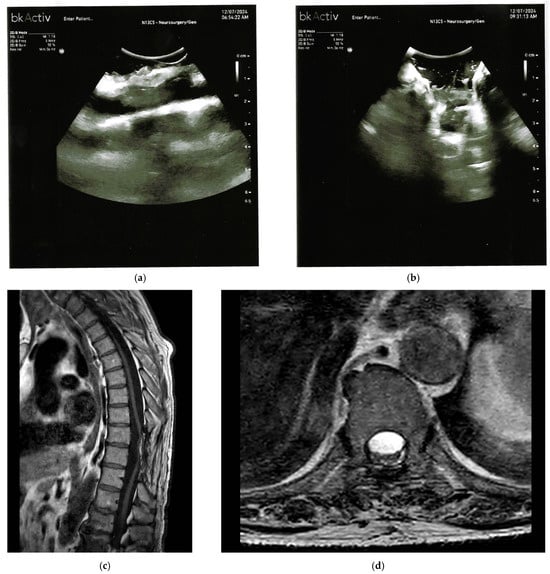

| Intradural Extramedullary Hemangioblastomas | Well circumscribed nodule with cystic components or syrinx; enhancing on contrast; associated with von Hippel Lindau disease. | Well defined, homogeneous, isoechoic nodule; cystic components; vascular profiling via Doppler or micro-Doppler for feeders or drainers. |